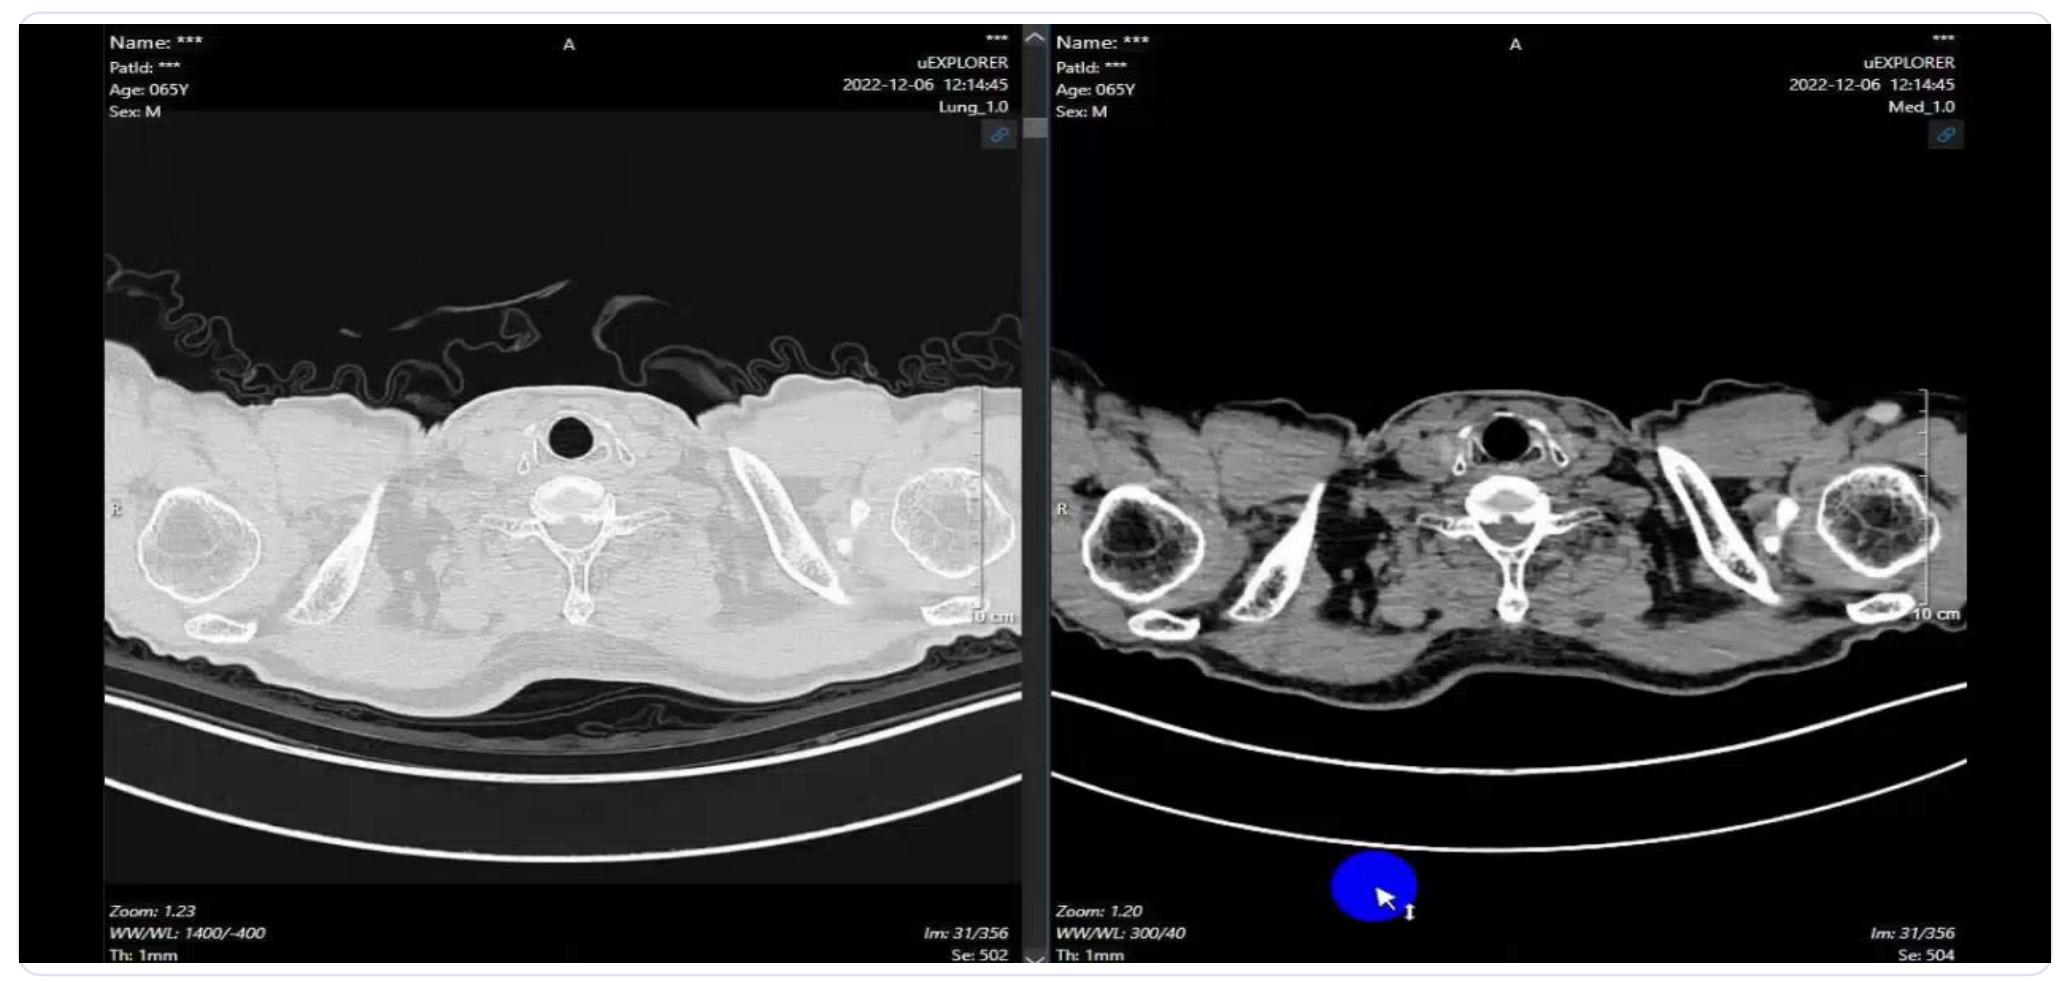

2022.12.4 疗效评估:PET/CT显示原发灶尺寸缩小(8.1×5.6 cm → 4.2×2.8 cm);SUVmax显著下降(21.8 → 5.3);多个淋巴结代谢活性明显降低